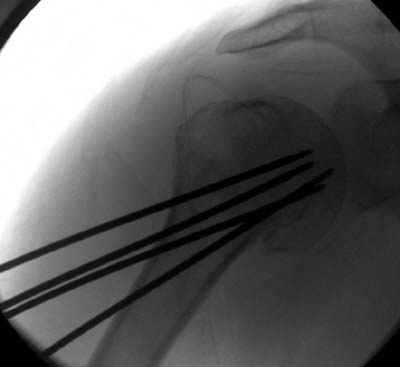

Женя, а как ты водишь спицы, в смысле, как делаешь входное отверстие, и как в него проводишь V-спицу? А то о дна из спиц, та, у которой не дошла до головки одна палочка буквы V, как-то выглядит на рентгенограмме, как будто или через очень большое отверстие введена, или каждая половинка через отдельные отверстия.

Спицы провожу по передней и задней поверхностям плечевой кости через 4,5 мм отверстия на разных уровнях.

Уточни - обе части буквы V вводишь в одно отверстие? А то по снимкам выглядит, что в разные.

V-спица проводится через 4,5 мм отверстие. Видимо, из-за разной длины вторая половина спицы *пролетела* мимо отверстия, что и привело к вторичному смещению костных фрагментов.